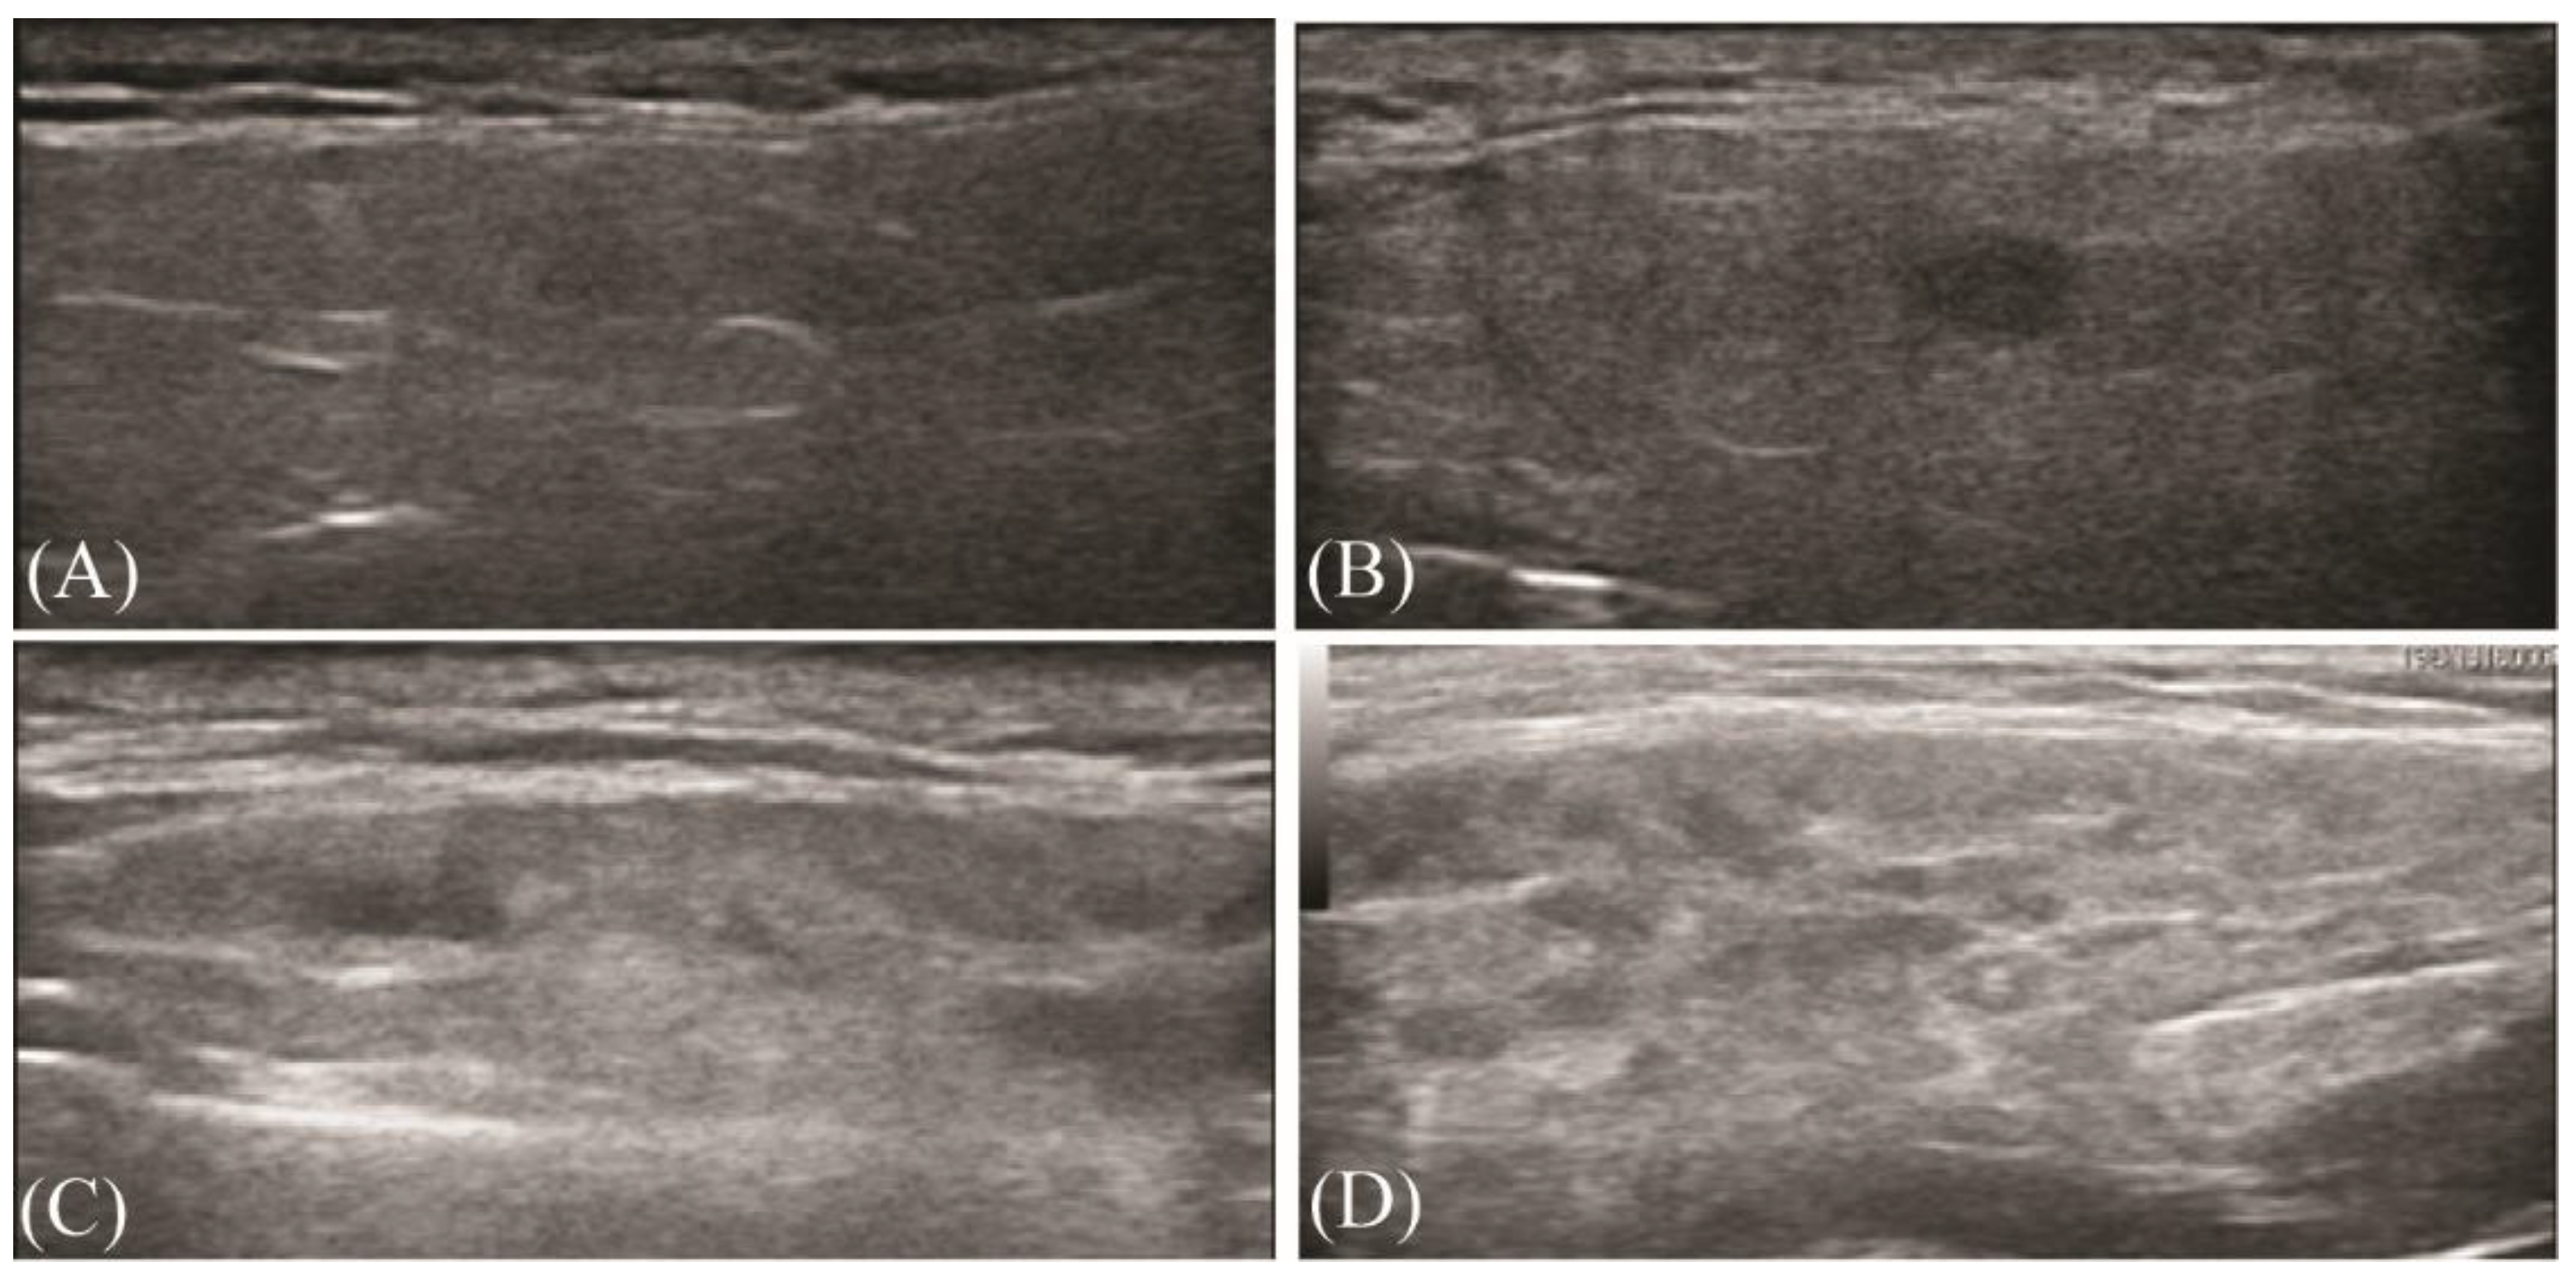

3.1. Ultrasonographic Evaluation of Major Salivary Glands